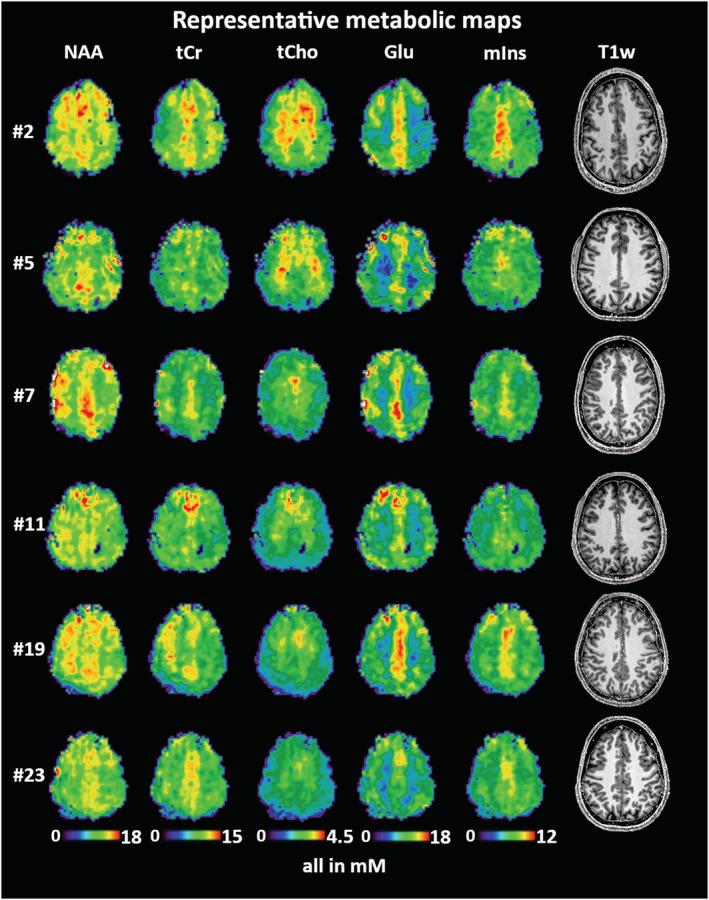

Inter-subject stability and regional concentration estimates of 3D-FID-MRSI in the human brain at 7 T.

We acquired whole-brain 3D-CRT-FID-MRSI at 7 T in 15 min with 3.4 mm nominal isometric resolution in 24 volunteers (12 male, 12 female, mean age 27 ± 6 years). Concentration estimate maps were calculated for 15 metabolites using internal water referencing and evaluated in 55 different regions of interest (ROIs) in the brain. Data quality, mean metabolite concentrations, and their inter-subject coefficients of variation (CVs) were compared for all ROIs.

Of 24 datasets, one was excluded due to motion artifacts. The concentrations of total choline, total creatine, glutamate, myo-inositol, and N-acetylaspartate in 44 regions were estimated within quality thresholds. Inter-subject CVs (mean over 44 ROIs/minimum/maximum) were 9%/5%/19% for total choline, 10%/6%/20% for total creatine, 11%/7%/24% for glutamate, 10%/6%/19% for myo-inositol, and 9%/6%/19% for N-acetylaspartate.